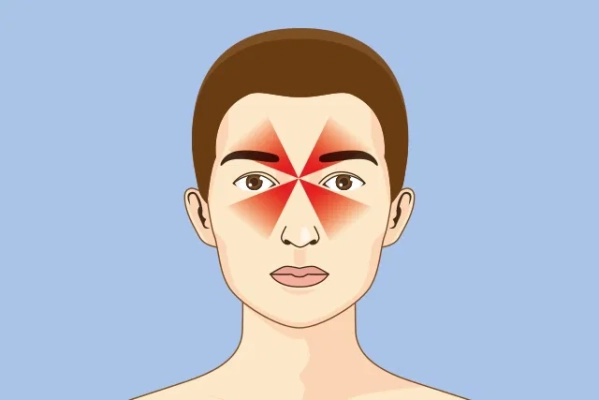

Dolor de cabeza por sinusitis

El dolor de cabeza por sinusitis es una manifestación clínica que se produce cuando los senos paranasales, cavidades llenas de aire ubicadas en el cráneo alrededor de la nariz y los ojos, se inflaman o se infectan. Esta inflamación genera acumulación de mucosidad y presión interna, lo que provoca dolor en la frente, alrededor de los ojos, en las mejillas o incluso en la parte superior de la cabeza. Es un tipo de cefalea secundaria, ya que se origina como consecuencia de una enfermedad subyacente, en este caso la sinusitis.

Dolor y presión en la frente, mejillas y alrededor de los ojos.